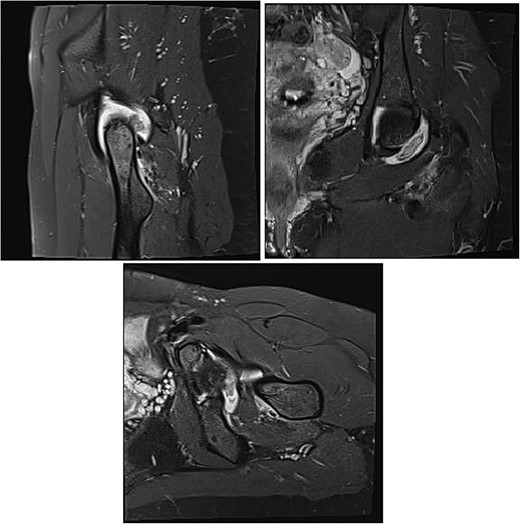

Magnetic resonance imaging (MRI) of the hip revealed a well-defined intra-articular mass with extensive synovial thickening (Fig. 1). Given these findings, the patient underwent hip arthroscopy to remove the mass and perform a histopathological examination.

MRI is observed in axial, sagittal, and coronal sections, showing the presence of an intra-articular lesion and abundant synovitis.